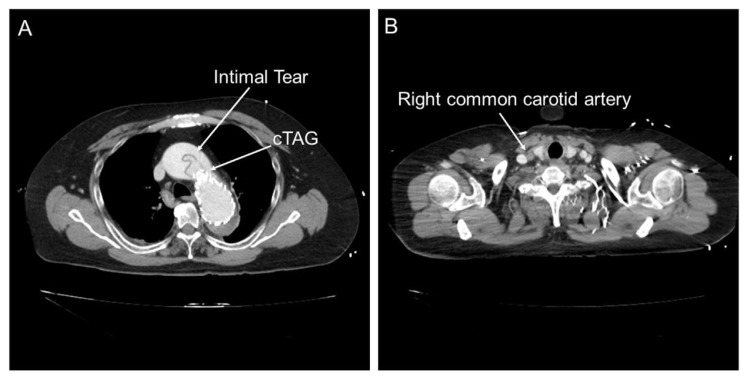

A 59-year-old male with prior thoracic endovascular aortic repair presented with altered mental status. Magnetic resonance imaging showed cerebral infarction, and subsequent computed tomography revealed acute type A aortic dissection and right carotid artery occlusion. He underwent total arch replacement with right carotid artery bypass. After successful intervention, he was transferred to a rehabilitation facility for further improvement.